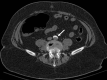

Coronavirus disease 2019 (COVID-19) is a multi-organ disease with a wide range of manifestations. Coagulopathy is one of the well-recognized complications of COVID-19. We report the case of a 42-year-old man who presented with progressively worsening low back pain of two days in duration. The pain was burning in character, non-radiating, and was not related to movement. The patient had a recent history of severe COVID-19 pneumonia requiring mechanical ventilation and has stayed in the intensive care unit for eight days. He was discharged three days before the acute onset of his back pain. Examination of the lumbar spine was unremarkable. However, lower limb examination revealed coldness and absent pulses bilaterally. The patient underwent computed tomography angiography which revealed complete occlusion of the lower abdominal aorta at its bifurcation. Emergency endovascular treatment was performed to aspirate the clot. The symptoms resolved following the procedure and the patient was discharged on the third post-intervention day. Saddle aortic embolism is a rare life-threatening condition that may present solely with low back pain. The case demonstrated a possible complication of COVID-19 that occurred after the recovery from the acute phase of the disease.